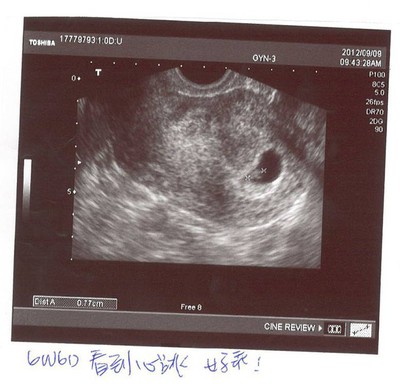

For my baby-9/9 心跳6W6D

6W6D.jpg 早上依舊去吃了早餐,但停好車要進醫院前,心裡突然難過了起來,似乎很難承受不知道接下來要面對什麼。今天早上人比較少,很快就輪到媽媽,一進診間,醫生很明確的認出媽媽,跟媽媽說等...